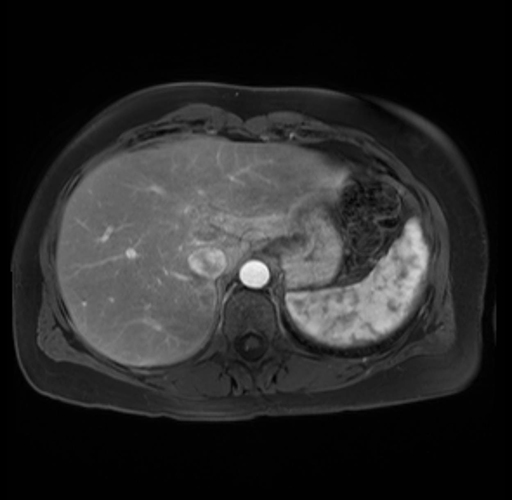

Imaging Analysis

Look through the patient's CT scan to identify any areas of concern for the necessary procedure.

Based on your CT findings, which issue(s) are present and would give reason for "planned slowing down moment(s)" in this case?